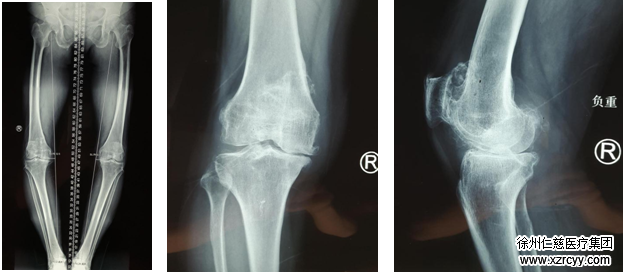

69岁的高老太是安徽宿州的农民,8年前,老人双腿膝盖开始疼痛,不能干农活,只能做点家务,儿女买来膏药给她敷贴,这些都只能暂时缓解膝盖的疼痛。一年两年过去,老人双膝疼痛的症状越来越重,2个月前,疼痛突然加剧,已经不能走远路了,出门都是一跛一跛的行走,干一点家务都比较困难了。

在必威官方首页官网betway关节科,邱东新组长详细给老人检查后,发现老人因为病史较长,双膝关节变形较为严重,已发展为晚期的骨性关节炎,已经无法行保膝治疗了,只能行膝关节置换手术。因为右膝关节疼痛更厉害,邱东新医师决定先进行导航下的右侧人工膝关节置换术。

长久以来,下肢力线一直被视作膝关节置换术的“生命线”,术中力线位置放置的准确与否极大程度上决定了患者术后的功能恢复,甚至假体的寿命。然而,传统手术中这一“生命线”的确定通过一个简单的导向杆定位完成,非常依赖于术者的经验判断及患者的解剖特征,术后力线的可重复性欠佳,尤其在面临关节外畸形等复杂患者时精确性更难以保障。计算机导航技术的出现为这一困境提供了最佳解决方案。

10月29日,邱东新组长手术团队为高老太进行了膝关节置换手术,凭借着高科技导航技术的指引,手术得以“化繁为简”,过程相当顺利,手术成功完成。术后患者假体位置良好,功能恢复十分满意。老人的罗圈腿也变直了。